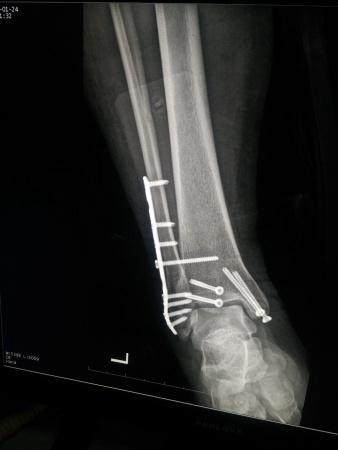

左三踝骨折手术治疗

患者女,外伤后左踝关节活动受限1小时入院,

入院后查体:左踝关节肿胀,活动受限,行DR及左踝关节CT检查,如下图,手术待肿胀消退后行手术治疗,目前愈合良好,请问问各位老师,好久可以下地呀, 下胫腓联合镙钉3个月取呀,

这个下胫腓螺钉真的没有必要打,另外后踝的两枚螺钉怪怪的,从后往前打的,看着钉子帽偏内侧,这个应该在外侧才对,

下胫腓联合单钉固定小心断钉